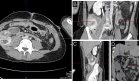

El ecocardiograma realizado el mismo día mostró disfunción ventricular izquierda moderada con una FEVI del 38%, asociada a discinesia apical y acinesia de los segmentos medio-distales de la pared anterior, distal de la pared inferior, medio-distales de la pared lateral y distal del septo interventricular posterior, configurando un patrón de balonamiento apical.

La presión sistólica de la arteria pulmonar fue de 60 mmHg, con regurgitación leve de la válvula tricúspide.

Una angiografía coronaria realizada también el día del ingreso no mostró lesiones significativas en las arterias coronarias epicárdicas. Ante el patrón ecocardiográfico y angiográfico, junto con la ausencia de enfermedad coronaria obstructiva, se diagnosticó una TM recurrente.